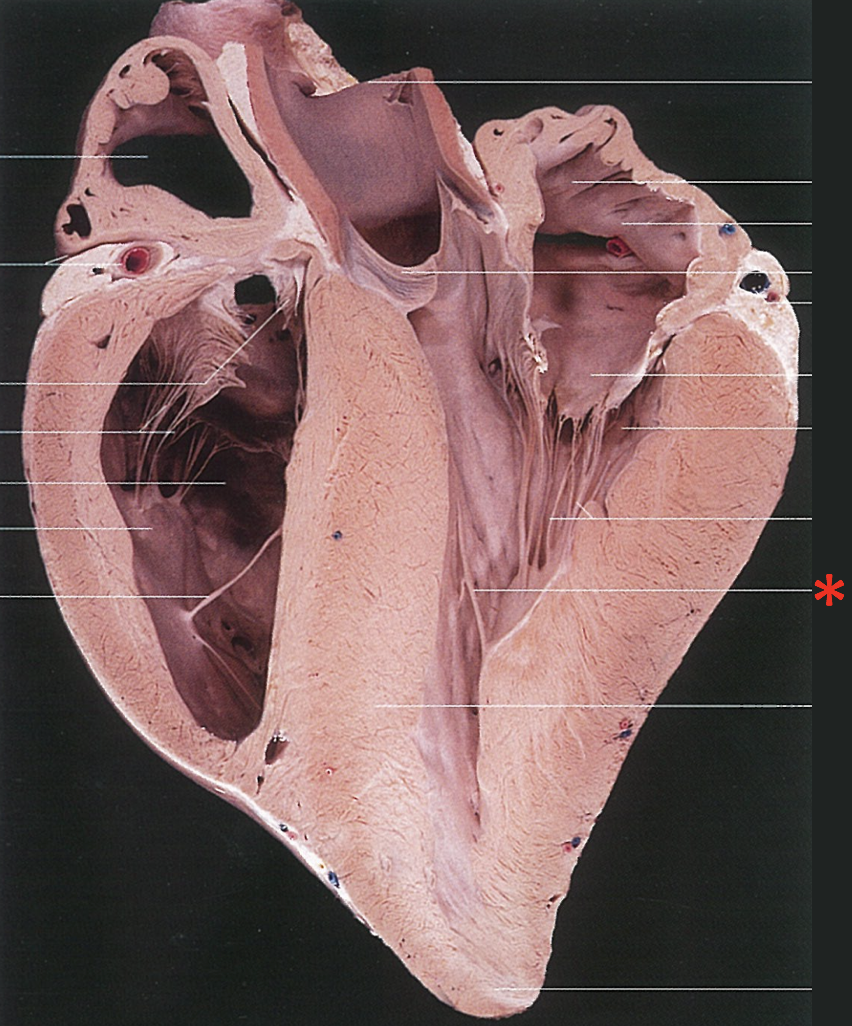

16

Left Semilunar Valvula

17

Parietal Cusp

18

Parietal Cup

19

Right Semilunar Valvula

Intermediate Semilunar Valvula

Septal Semilunar Valvula